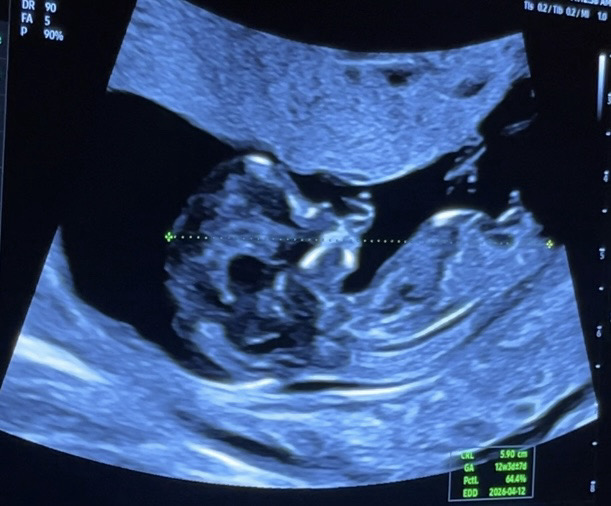

12주에요 각도법 좀 봐주세여

성별 너무궁금해요 ㅠ 도와주세요!!